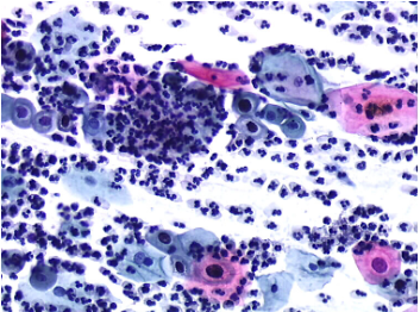

Figs 1 and 2 from a mass in the right hypochondriac region.

Make your diagnosis.

Fig 1 : Giemsa x 100

Fig 2 : Giemsa x 400